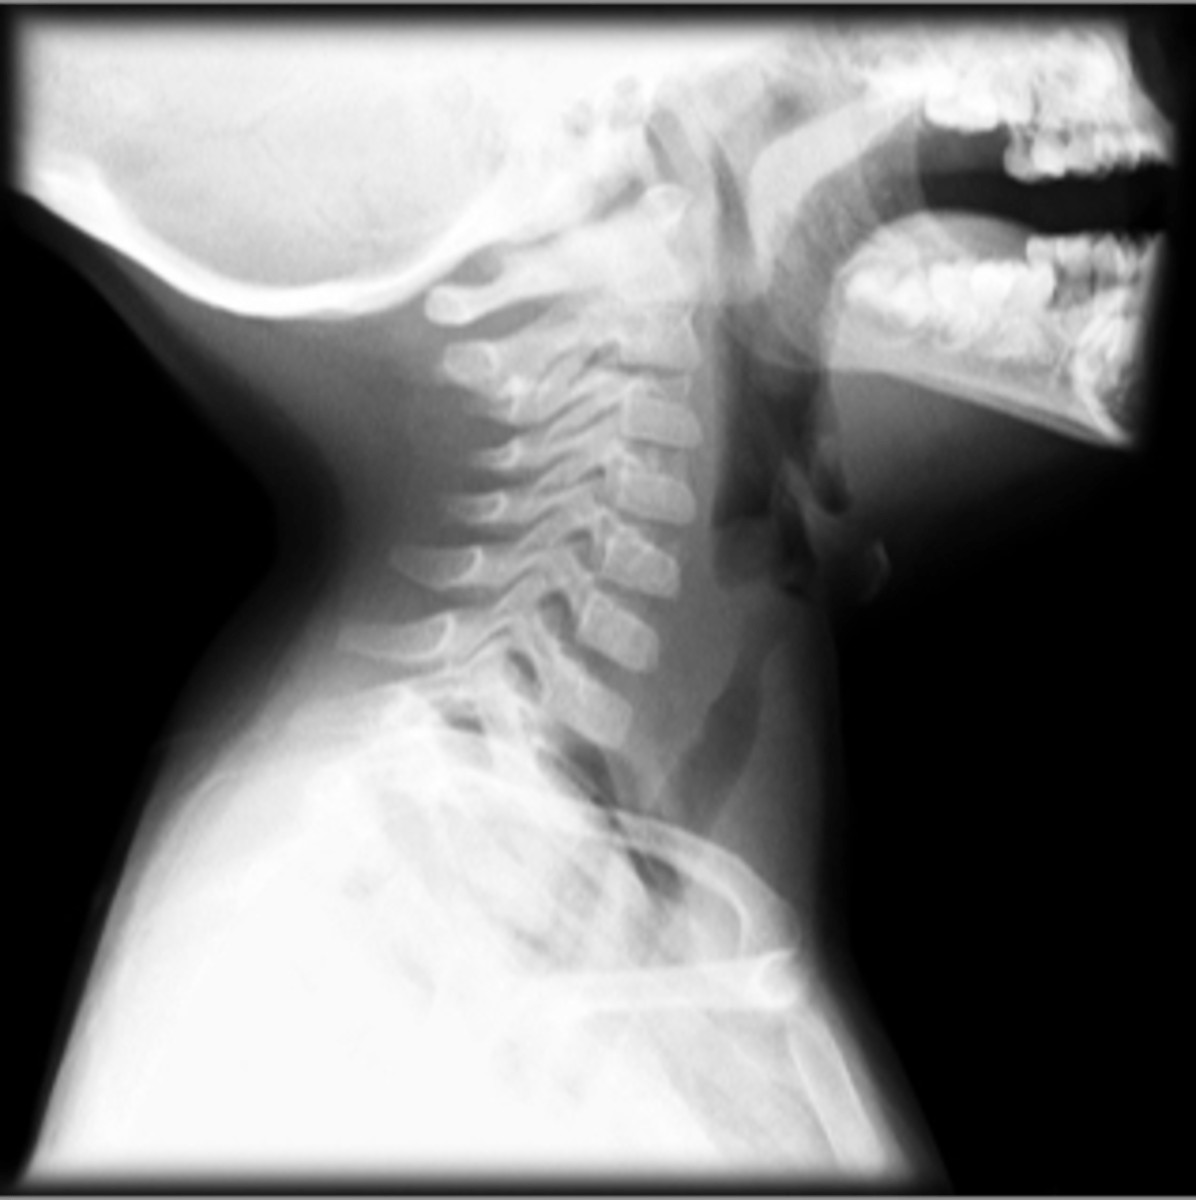

Epiglottitis (thumb sign)

steeple sign (croup)

steeple sign (croup)

Croup

Steeple sign- group